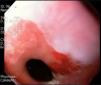

Mujer de 53 años, sin antecedentes de importancia, quien ingresa a urgencias por 2 días de hematemesis sin dolor abdominal; en el examen físico se registra una frecuencia cardíaca de 90 con presión arterial de 100/60 y tacto rectal positivo para melenas. Fue llevada a endoscopia, donde se observa una unión gastroesofágica sin alteraciones (fig. 1) y 2 dilataciones venosas en el tercio proximal del esófago, sin evidencia del sangrado activo (fig. 2), indicativo de cuadro de varices en Downhill, por lo que se realizó tomografía computarizada de tórax que mostró imagen de trombo en vena cava superior (fig. 3). Se inició manejo con anticoagulación con enoxaparina, con posterior control endoscópico a las 72h, el cual mostró disminución del tamaño de las varices esofágicas. Se iniciaron estudios de hipercoagulabilidad, los cuales fueron normales a excepción de la mutación de factor V de Leiden.